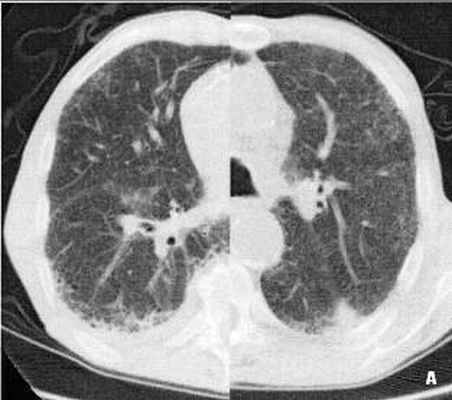

Рис. 1 (А, Б, В). КТВР больного С., 66 лет. Организующая пневмония на фоне обычной интерстициальной пневмонии.

А - Комбинированный фрагмент КТВР легких на уровне нижней доли правого и верхней доли левого легкого. В правом легком - многочисленные мелкие субплевральные полости, расположенные рядами, единичные тракционные бронхоэктазы, в левом легком - в заднем сегменте верхней доли слева на границе нормальной и измененной паренхимы субплевральная треугольная консолидация, с широким основанием к костальной плевре, структура ее однородная. Б – МПР левого легкого в коронарной проекции на уровне консолидации. При МПР субплевральная консолидация представляется треугольной конусовидной, т.е. не меняет пространственной конфигурации. Проведена морфологическая верификация консолидации под КТ-контролем получены клетки воспаления (макрофаги, незрелые фибробласты). Полученные данные соответствуют организующей пневмонии на фоне обычной интерстициальной пневмонии в стадии начального фиброза. В - динамическое наблюдение после лечения спустя 4 недели после исследования, представленного на рисунке 1А. Фрагмент КТВР легких на уровне верхних долей легких. Отмечается полное восстановление пневматизации на месте ранее выявляемой консолидации слева.